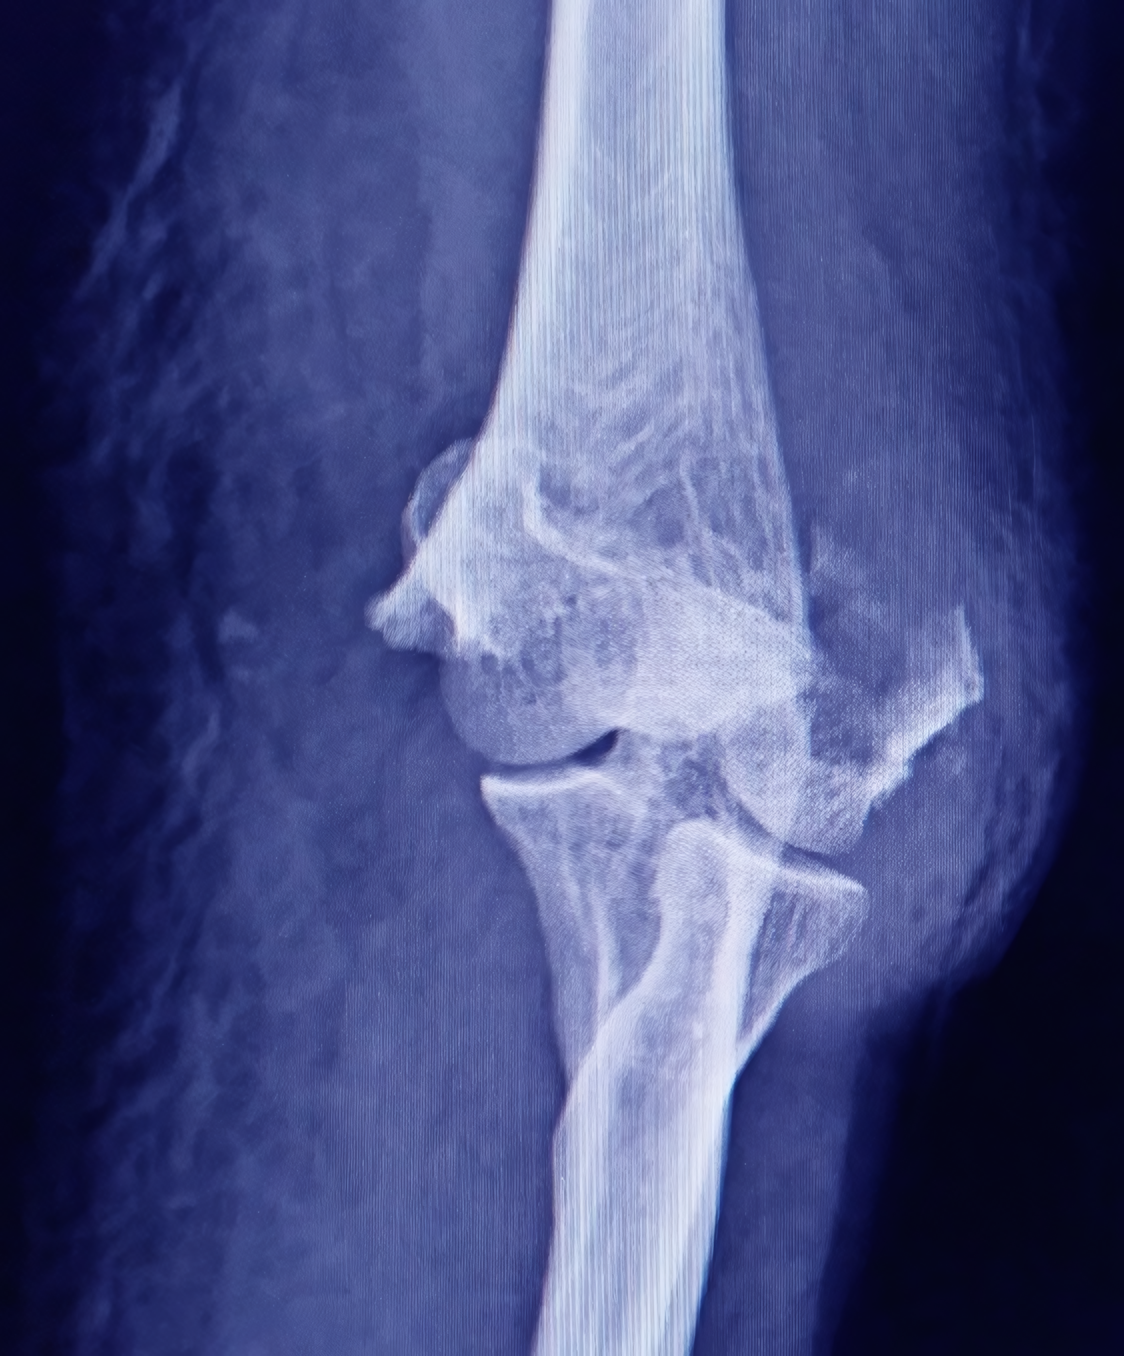

El área de trauma ortopédico se especializa en la atención de pacientes que han sufrido fracturas, luxaciones o lesiones complejas derivadas de caídas, accidentes laborales, deportivos o de tránsito. Nuestro equipo interdisciplinario aplica protocolos de atención inmediata para reducir riesgos y complicaciones, ofreciendo desde tratamientos conservadores hasta procedimientos quirúrgicos avanzados. Además, acompañamos el proceso de recuperación con terapias orientadas a recuperar la movilidad y prevenir secuelas.

¿Cómo sé si una lesión necesita atención ortopédica inmediata?

Debes consultar de urgencia si presentas dolor intenso, deformidad visible, incapacidad para mover la extremidad, inflamación excesiva, hematomas grandes o si la lesión está asociada a un accidente de alto impacto. Una atención temprana evita complicaciones y mejora la recuperación.